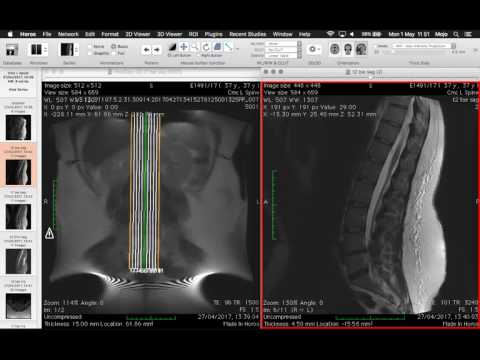

All this resting malarky is boring so I made a video of some of the MRI images on the CD given to me by the clinic. I love seeing X-Rays, scans etc, especially my own :-)